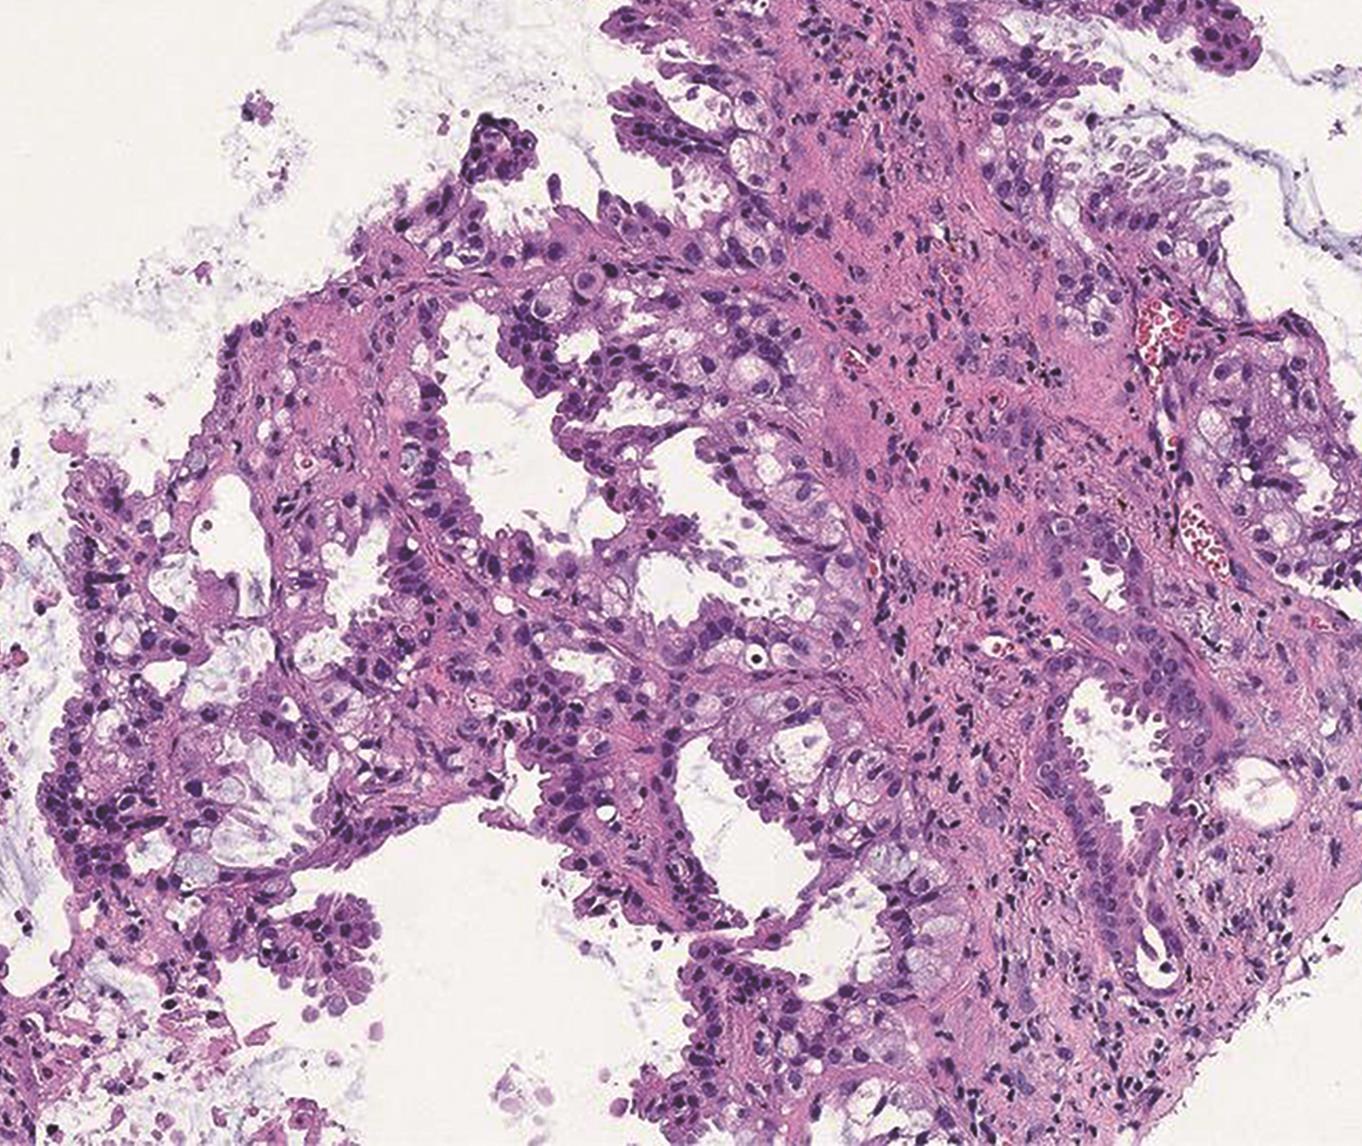

• 靶点靶线体表描记法在CT引导经皮肺穿刺活检术中的应用

2023, 48(9):1133-1137. DOI: 10.13406/j.cnki.cyxb.003328

摘要 (93) HTML (23) PDF 2.14 M (224) 评论 (0) 收藏

摘要:目的 旨在探讨靶点靶线体表描记法在CT引导经皮肺穿刺活检术中的技术要点及应用价值。方法 选取2021年8月至2022年4月进行肺穿刺活检的病例152例,随机分为A组(77例,采用靶点靶线体表描记法穿刺)和B组(75例,常规穿刺法),比较2组首次进针成功率、CT扫描次数、诊断准确率、术后并发症及手术时间以评估2种手术方法效果。结果 2组均穿刺成功并取得标本,穿刺成功率均为100%。首次进针成功:A组64例,B组62例,2组间无统计学差异(χ=0.005,P=0.941);CT扫描次数超标:A组18例,B组54例,2组间有统计学差异(χ=36.030,P<0.05);诊断准确:A组70例,B组68例,2组间无统计学差异(χ=0.003,P=0.959);咯血:A组12例,B组9例,2组间无统计学差异(χ=0.410,P=0.522);气胸:A组10例,B组11例,2组间无统计学差异(χ=0.090,P=0.764);手术时间:A组平均(19.88±4.47) min,B组平均(32.23±4.95) min,2组间有统计学差异(t检验,P<0.05)。结论 CT引导肺穿刺术中应用靶点靶线体表描记法简单易行,能准确指导CT引导肺穿刺术中穿刺角度的把握,减少术中CT扫描次数,值得在临床中推广。